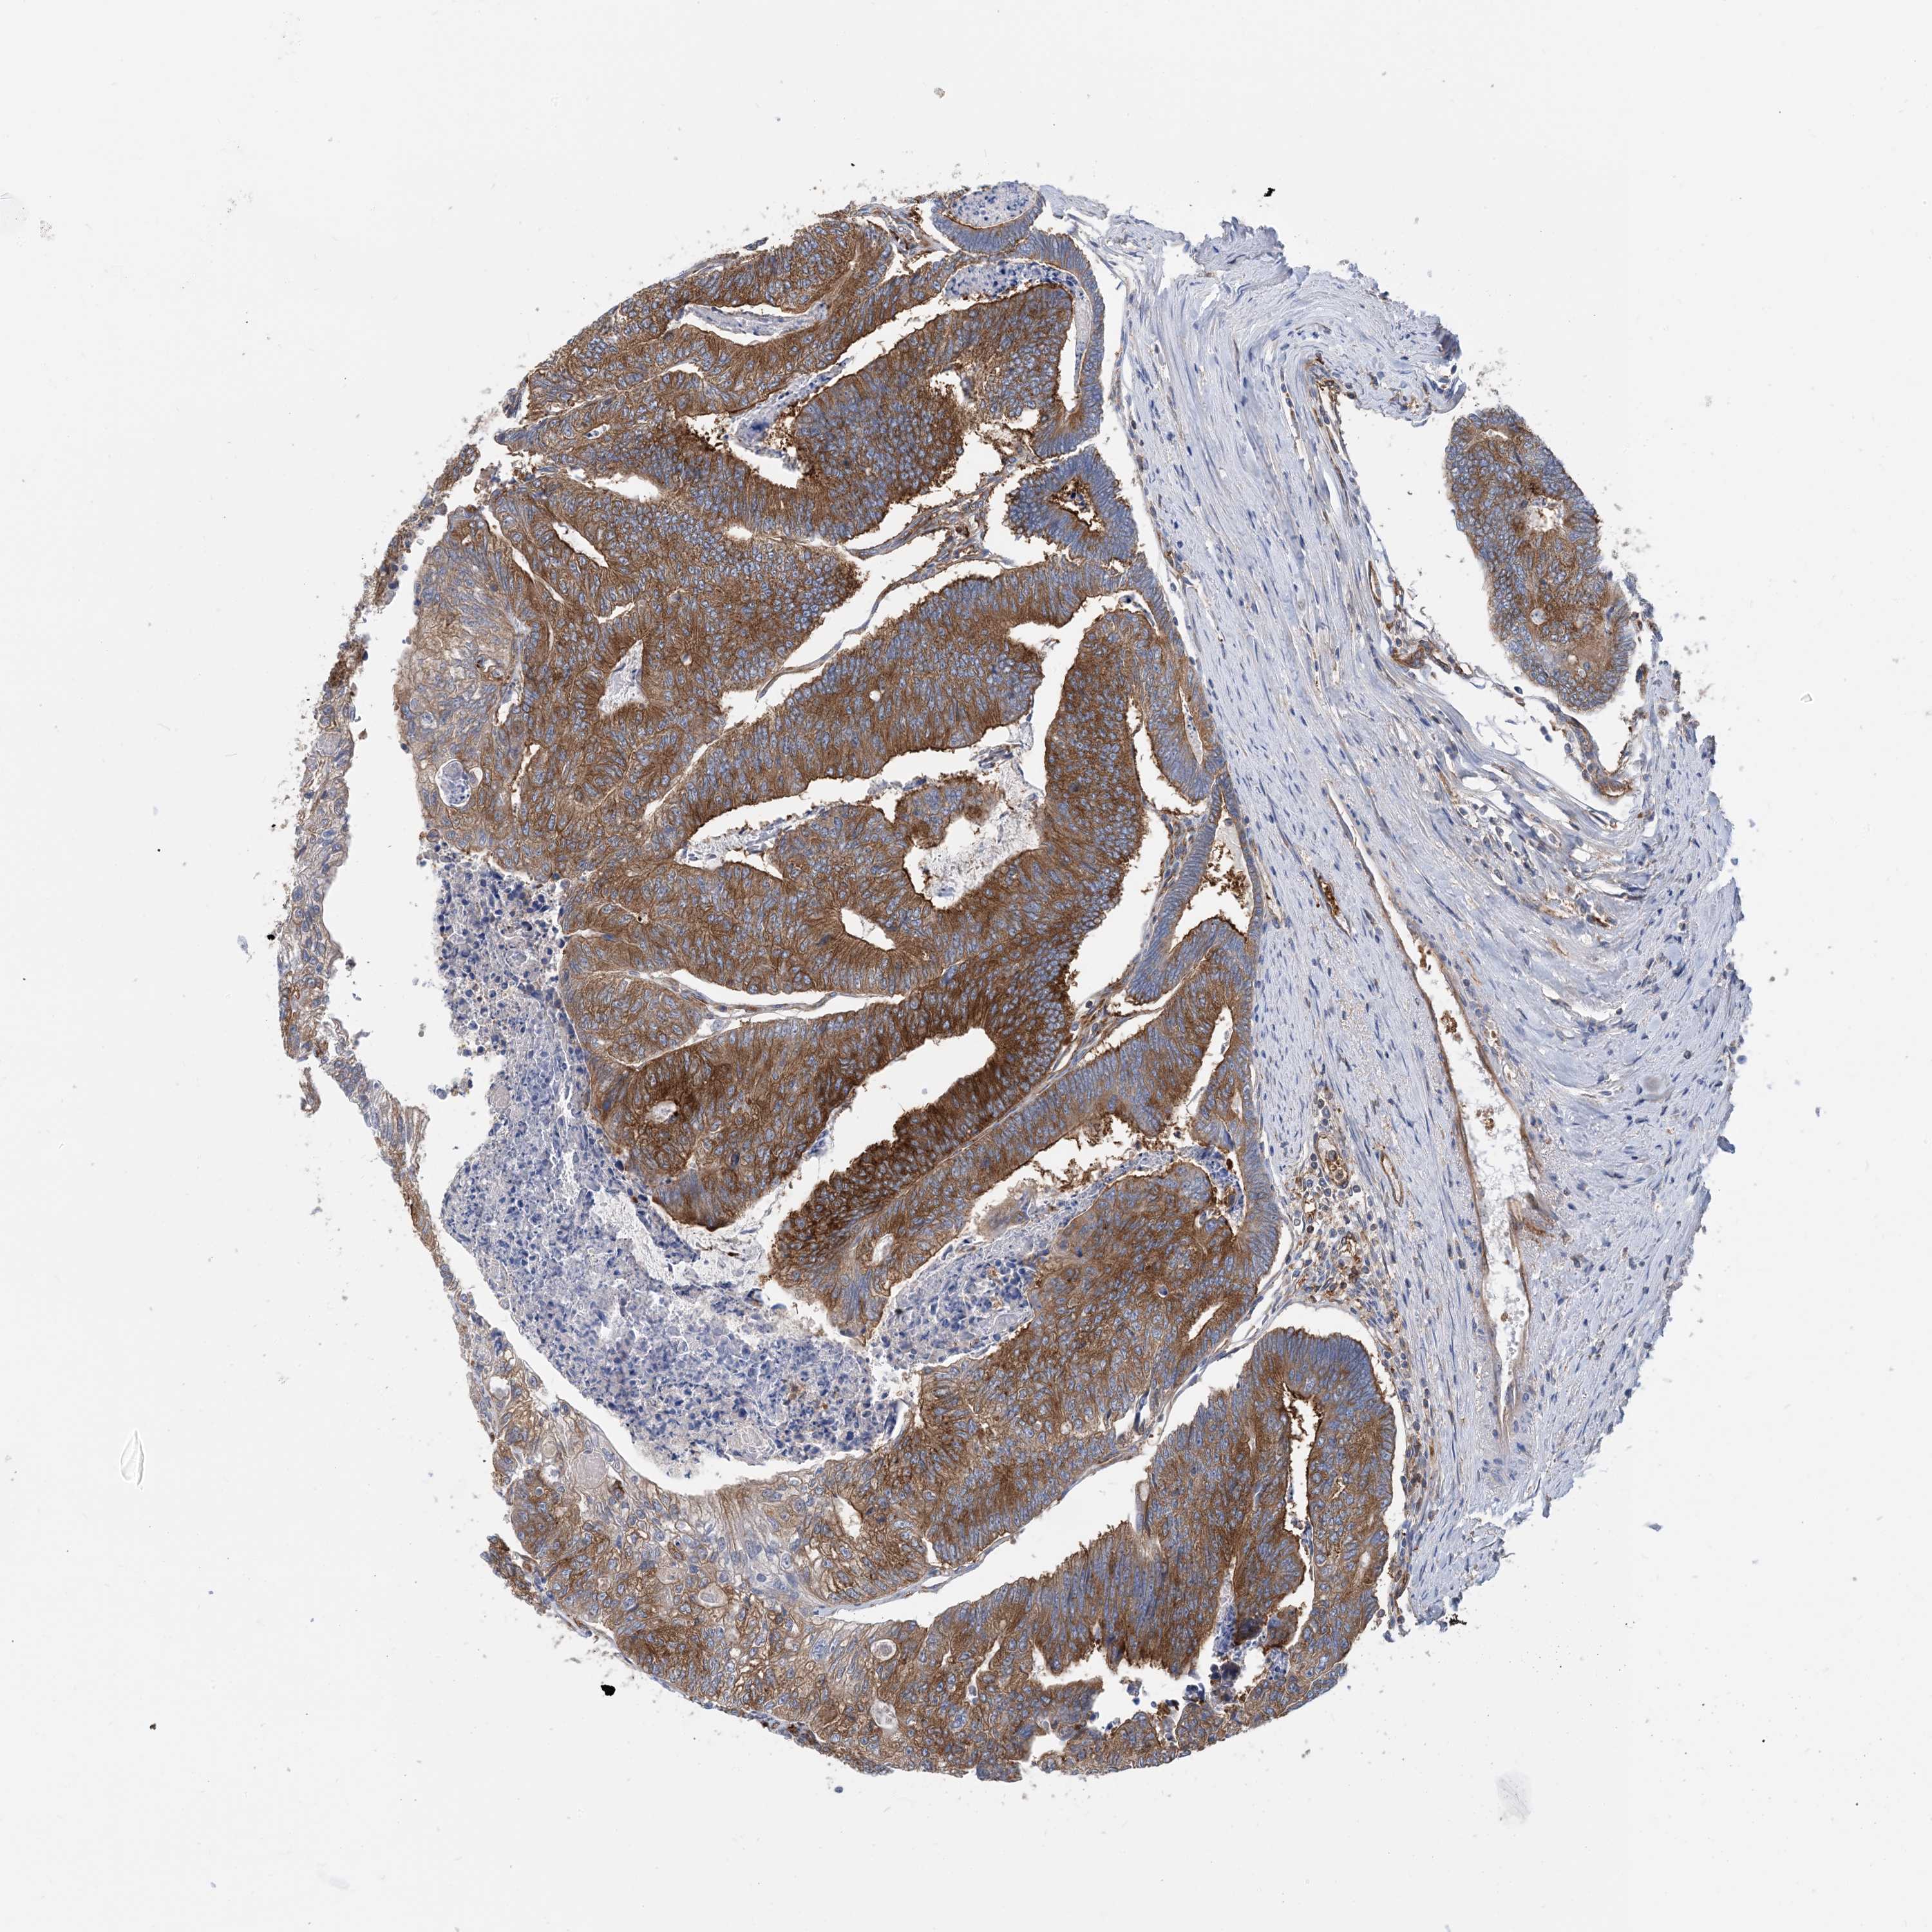

CANCER COLORECTAL CANCER Show tissue menu

Colorectal cancer

Human cancer

Colon adenocarcinoma